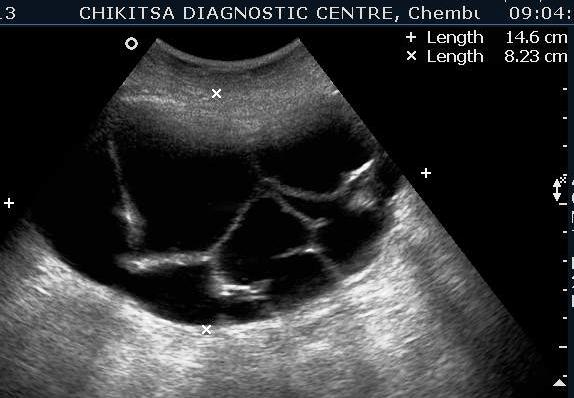

A 35 year old female was referred to our centre by a gynaecologist with gradually increasing distension abdomen & discomfort ,with pressure downwards. She had two alive children , both delivered normally & one early abortion , now tubectomised for 5 years.She had normal regular periods with cycle 3-5/25-35 days. No history of dysmenorrhoea.No history of any chronic medical illness. On ultrasound abdominally, one large mass of 15 cm x 10 cm with multiple septations was seen. On colour flow, vascularity was noted in the septal walls. No papillary projections seen in the mass.No solid areas seen in the mass.Uterus & right ovary were found to be normal. Diagnosis of left benign ovarian tumour ? mucinous cystadenoma was made which was confirmed on HPE after left ovariotomy .

Multiple thin septae are present and low levels echoes due to mucoid material present in the dependant portions of the mass. In mucinous Cystadenomas, individual locules may vary in imaging appearance due to difference in degree of hemorrhage and protein content. That's the differentiating point between serous and mucinous. Smooth inner wall structures are more reliable characteristics in predicting benignity. Presence of solid components and lesion without measurable wall thickness and demonstrable inner wall structure suggested malignancy. The difference in chemical components and difference in viscosity is responsible for sonographic echogenicity.

Identification of papillary projections on an imaging study is important because they are the single best predictor of the epithelial character of a neoplasm and may correlate with the aggressiveness of the tumor.

Absence of ascitis favoured benign lesions and its presence meant more chances of the lesion being malignant.